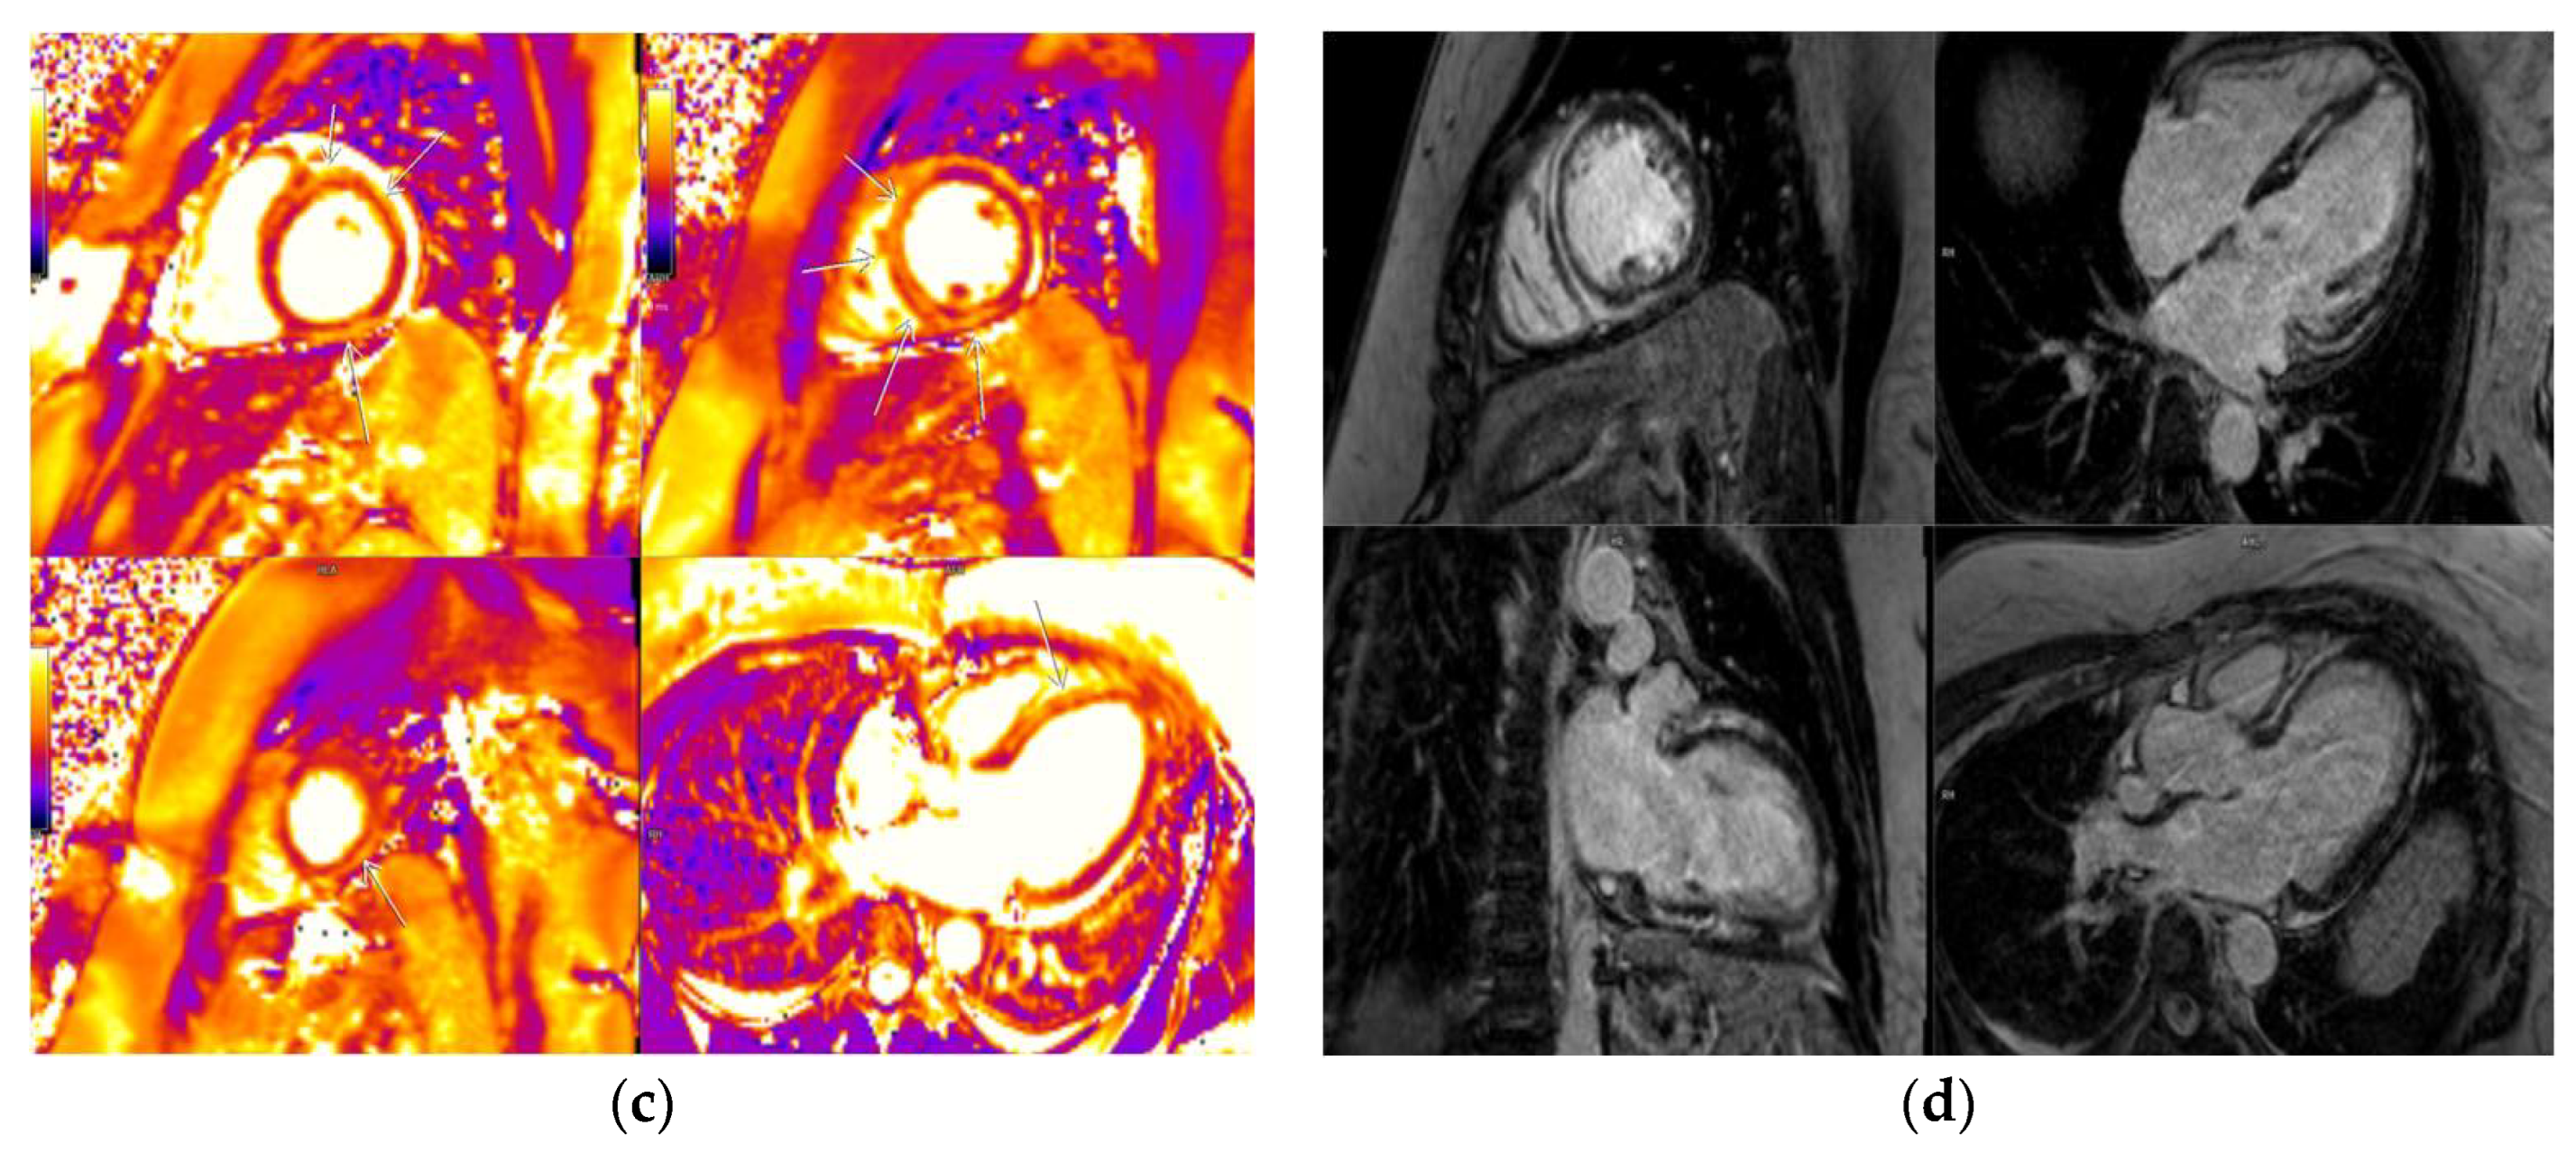

3.2. CMR Findings

3.5. LGE Localization

| T1 mappingvalues | 1063.5 ± 9.7 ms | 1103.9 ± 17.2 ms | p = 0.033 | t = −2.2 | Yes |